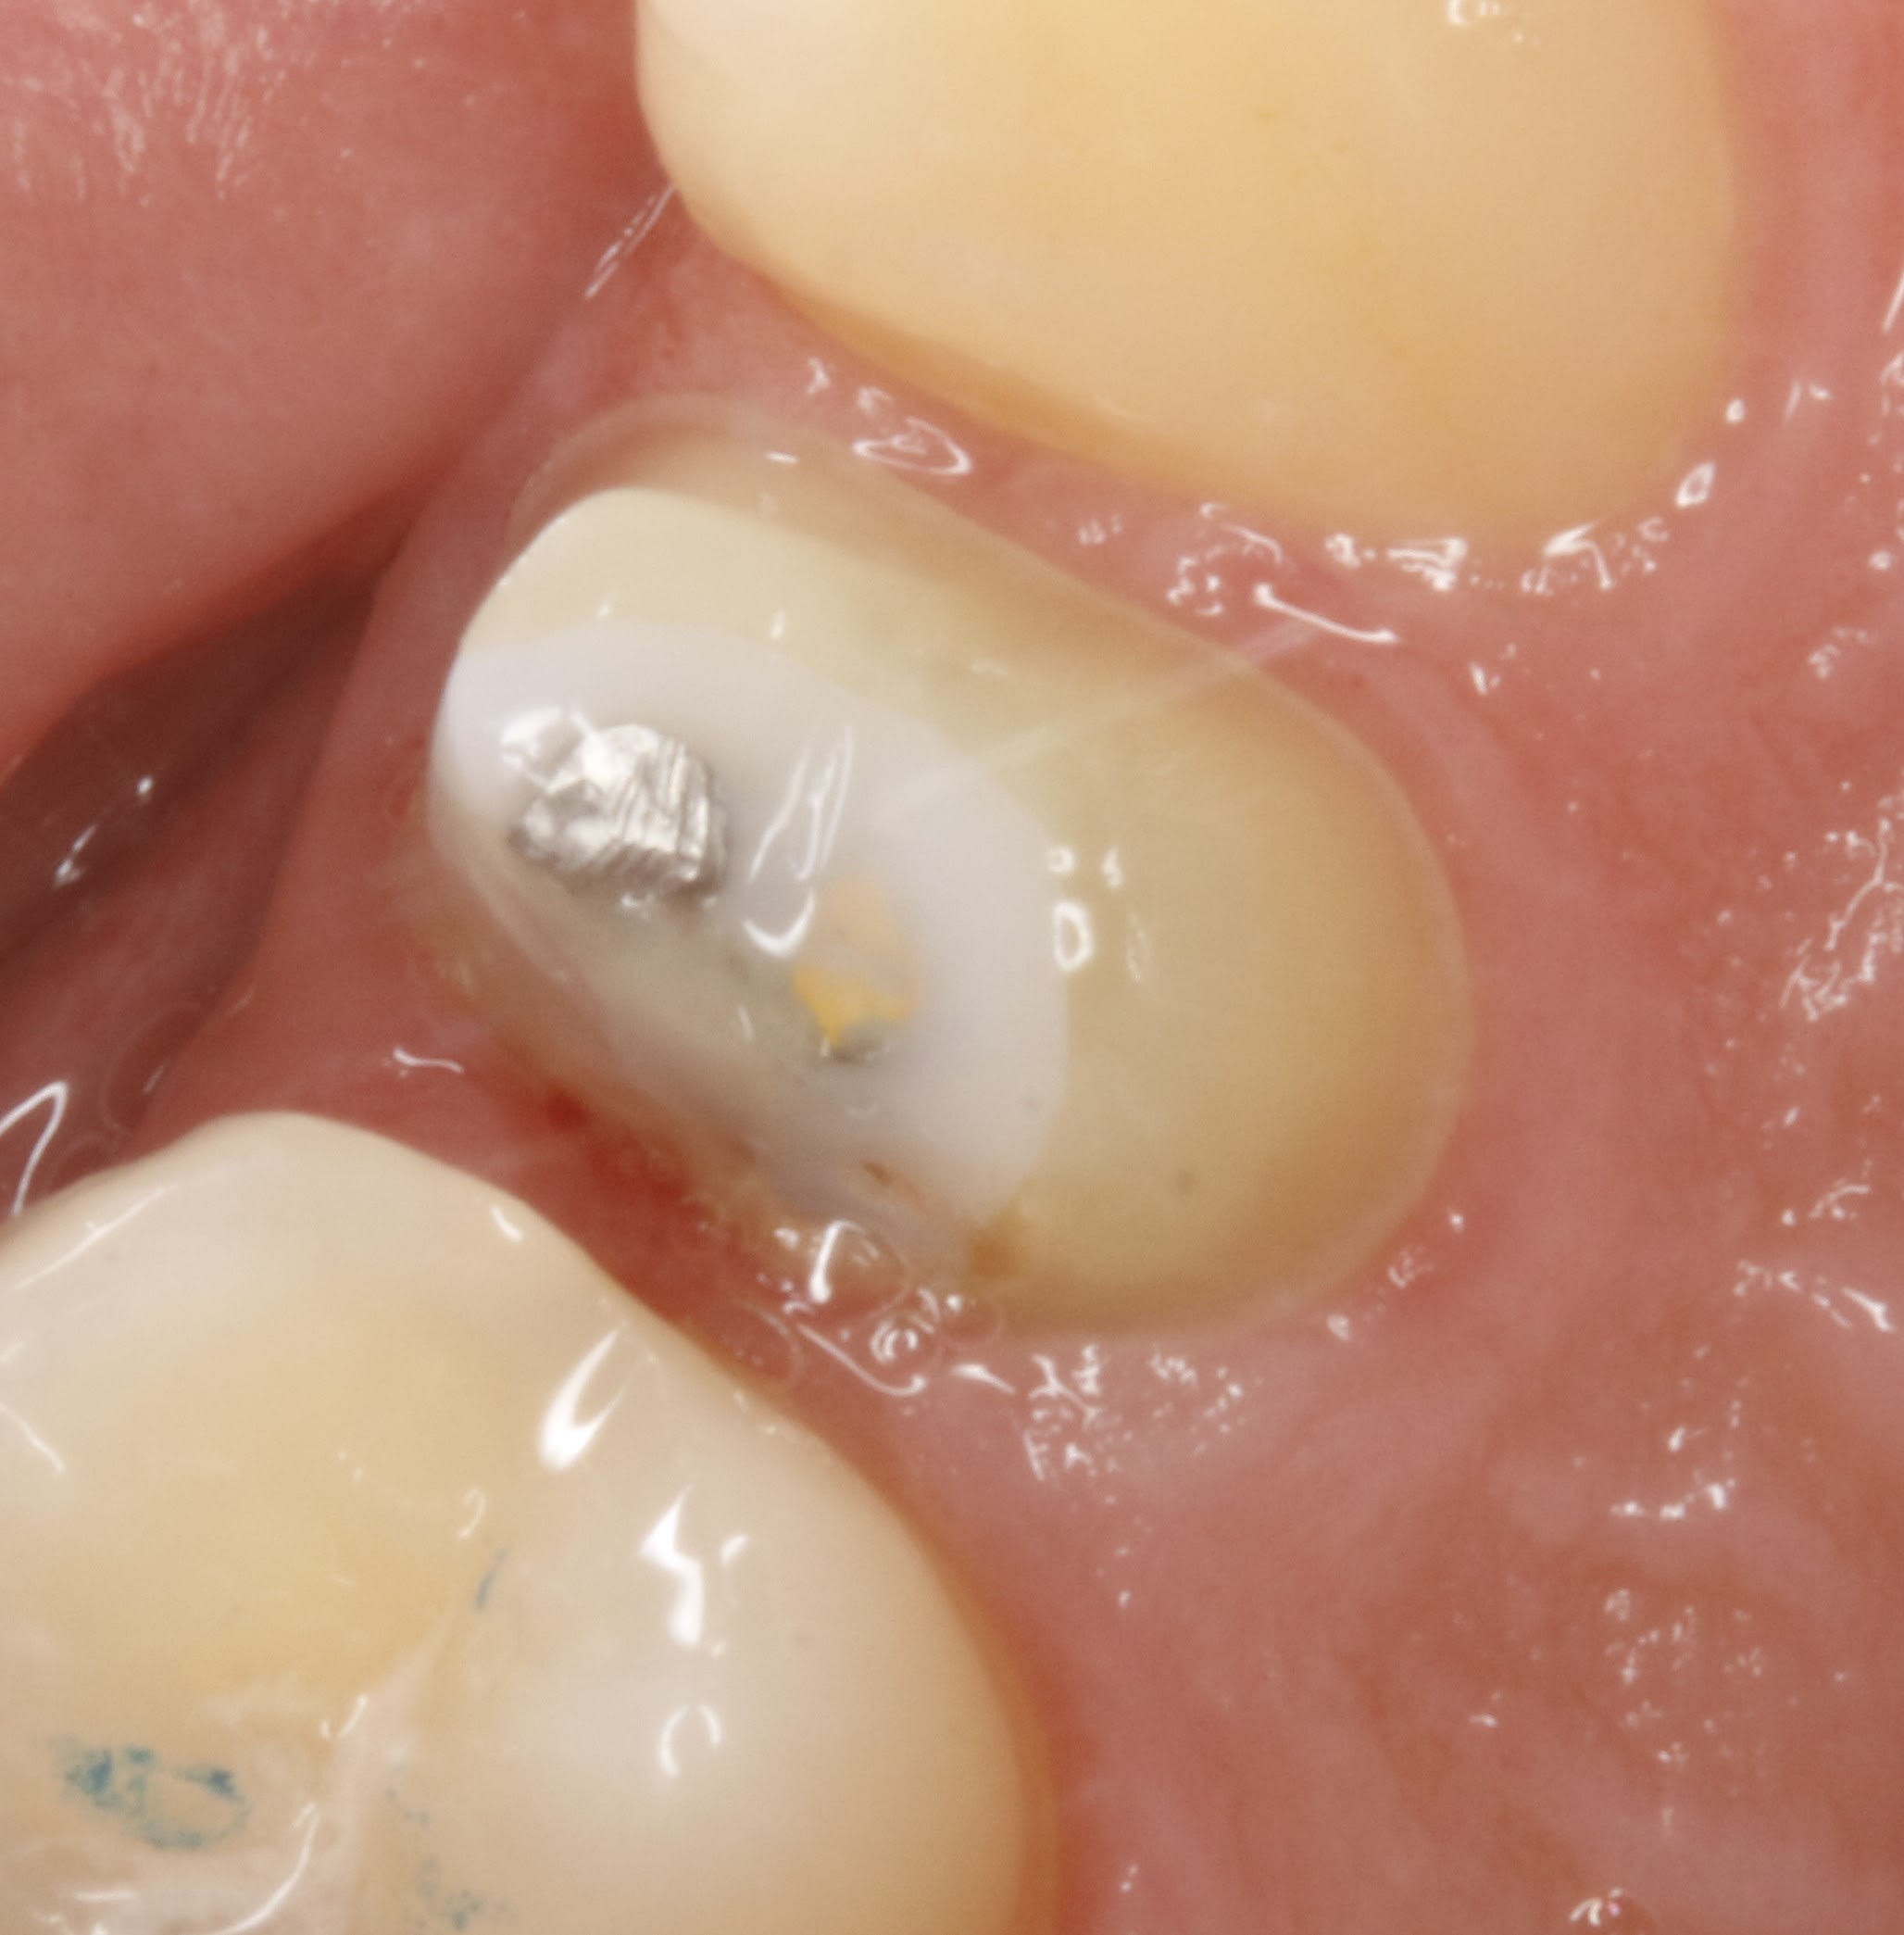

une dernière d aujourd'hui .

le cas de départ était profond pour un jeune . il est resté des mois avec son pansement et ça saigne volontiers

4xayrlvj92rwvh98nmb53lles8ks - Eugenol

et le plus simple était de couper la papille emboucanée et là on est à 3 semaines sans prov , aujourd'hui c est le jour de la pose .